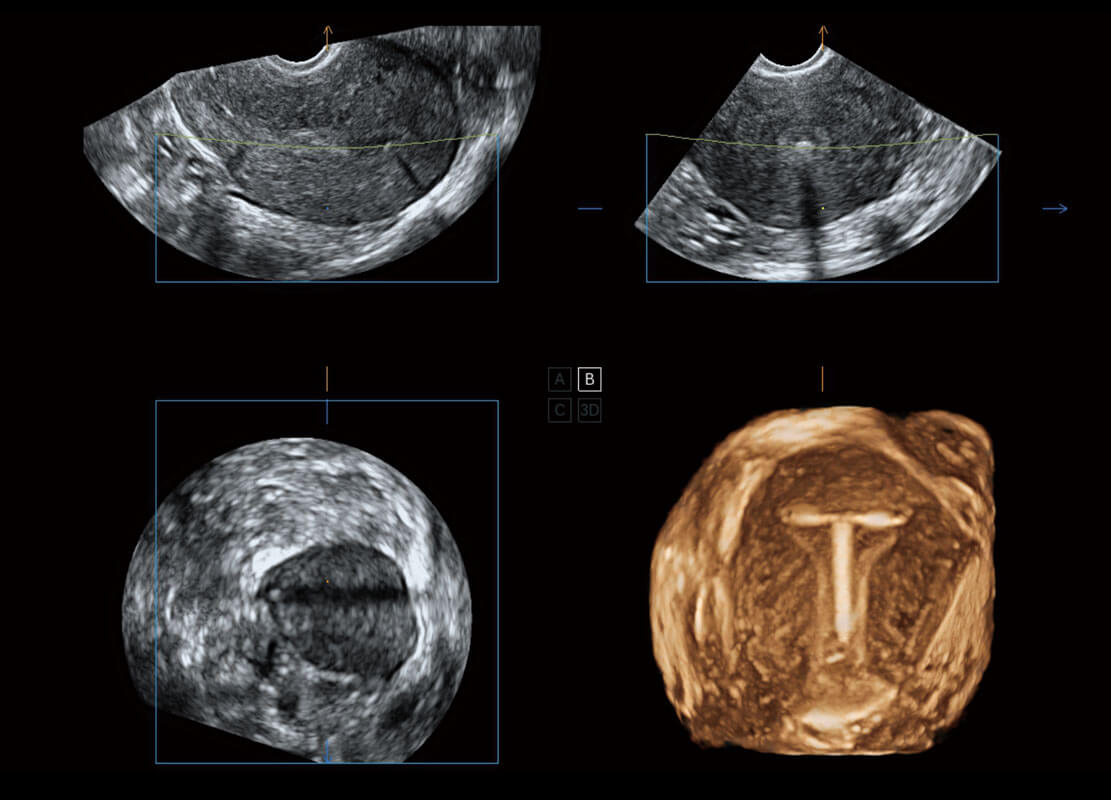

腔内三维-宫内节育器

腔内三维-光影成像

P60为盆底超声检查提供应用方案,多种腔内及腹部容积探头提供从二维、三维到四维的优异图像品质,实时快速三维容积数据获取,专业的测量工具包等人性化设计,为超声医生诊断提供有力保障。

能够简化盆底检查的操作流程,可在二维模式及三维成像模式下实现一键自动提取出标准切面、自动识别当前切面、自动测量,提升盆底检查的高效性,同时也能让青年医生快捷的获得准确的检查结果。